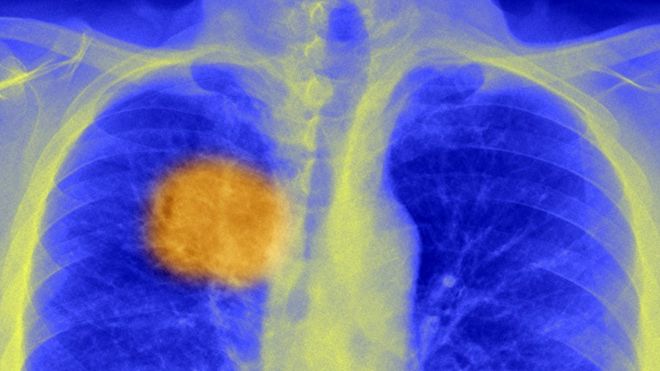

Part of the problem is that cancer cells are not identical at all. Indeed, they have been found to be extremely mutated. They are generally described as being like a tree with “trunk” mutations, these mutations branch off in different directions, which is known as cancer heterogeneity.

The new study shows a way of discovering the “trunk” mutations that change antigens, which are proteins that stick out of the surface of cancer cells.